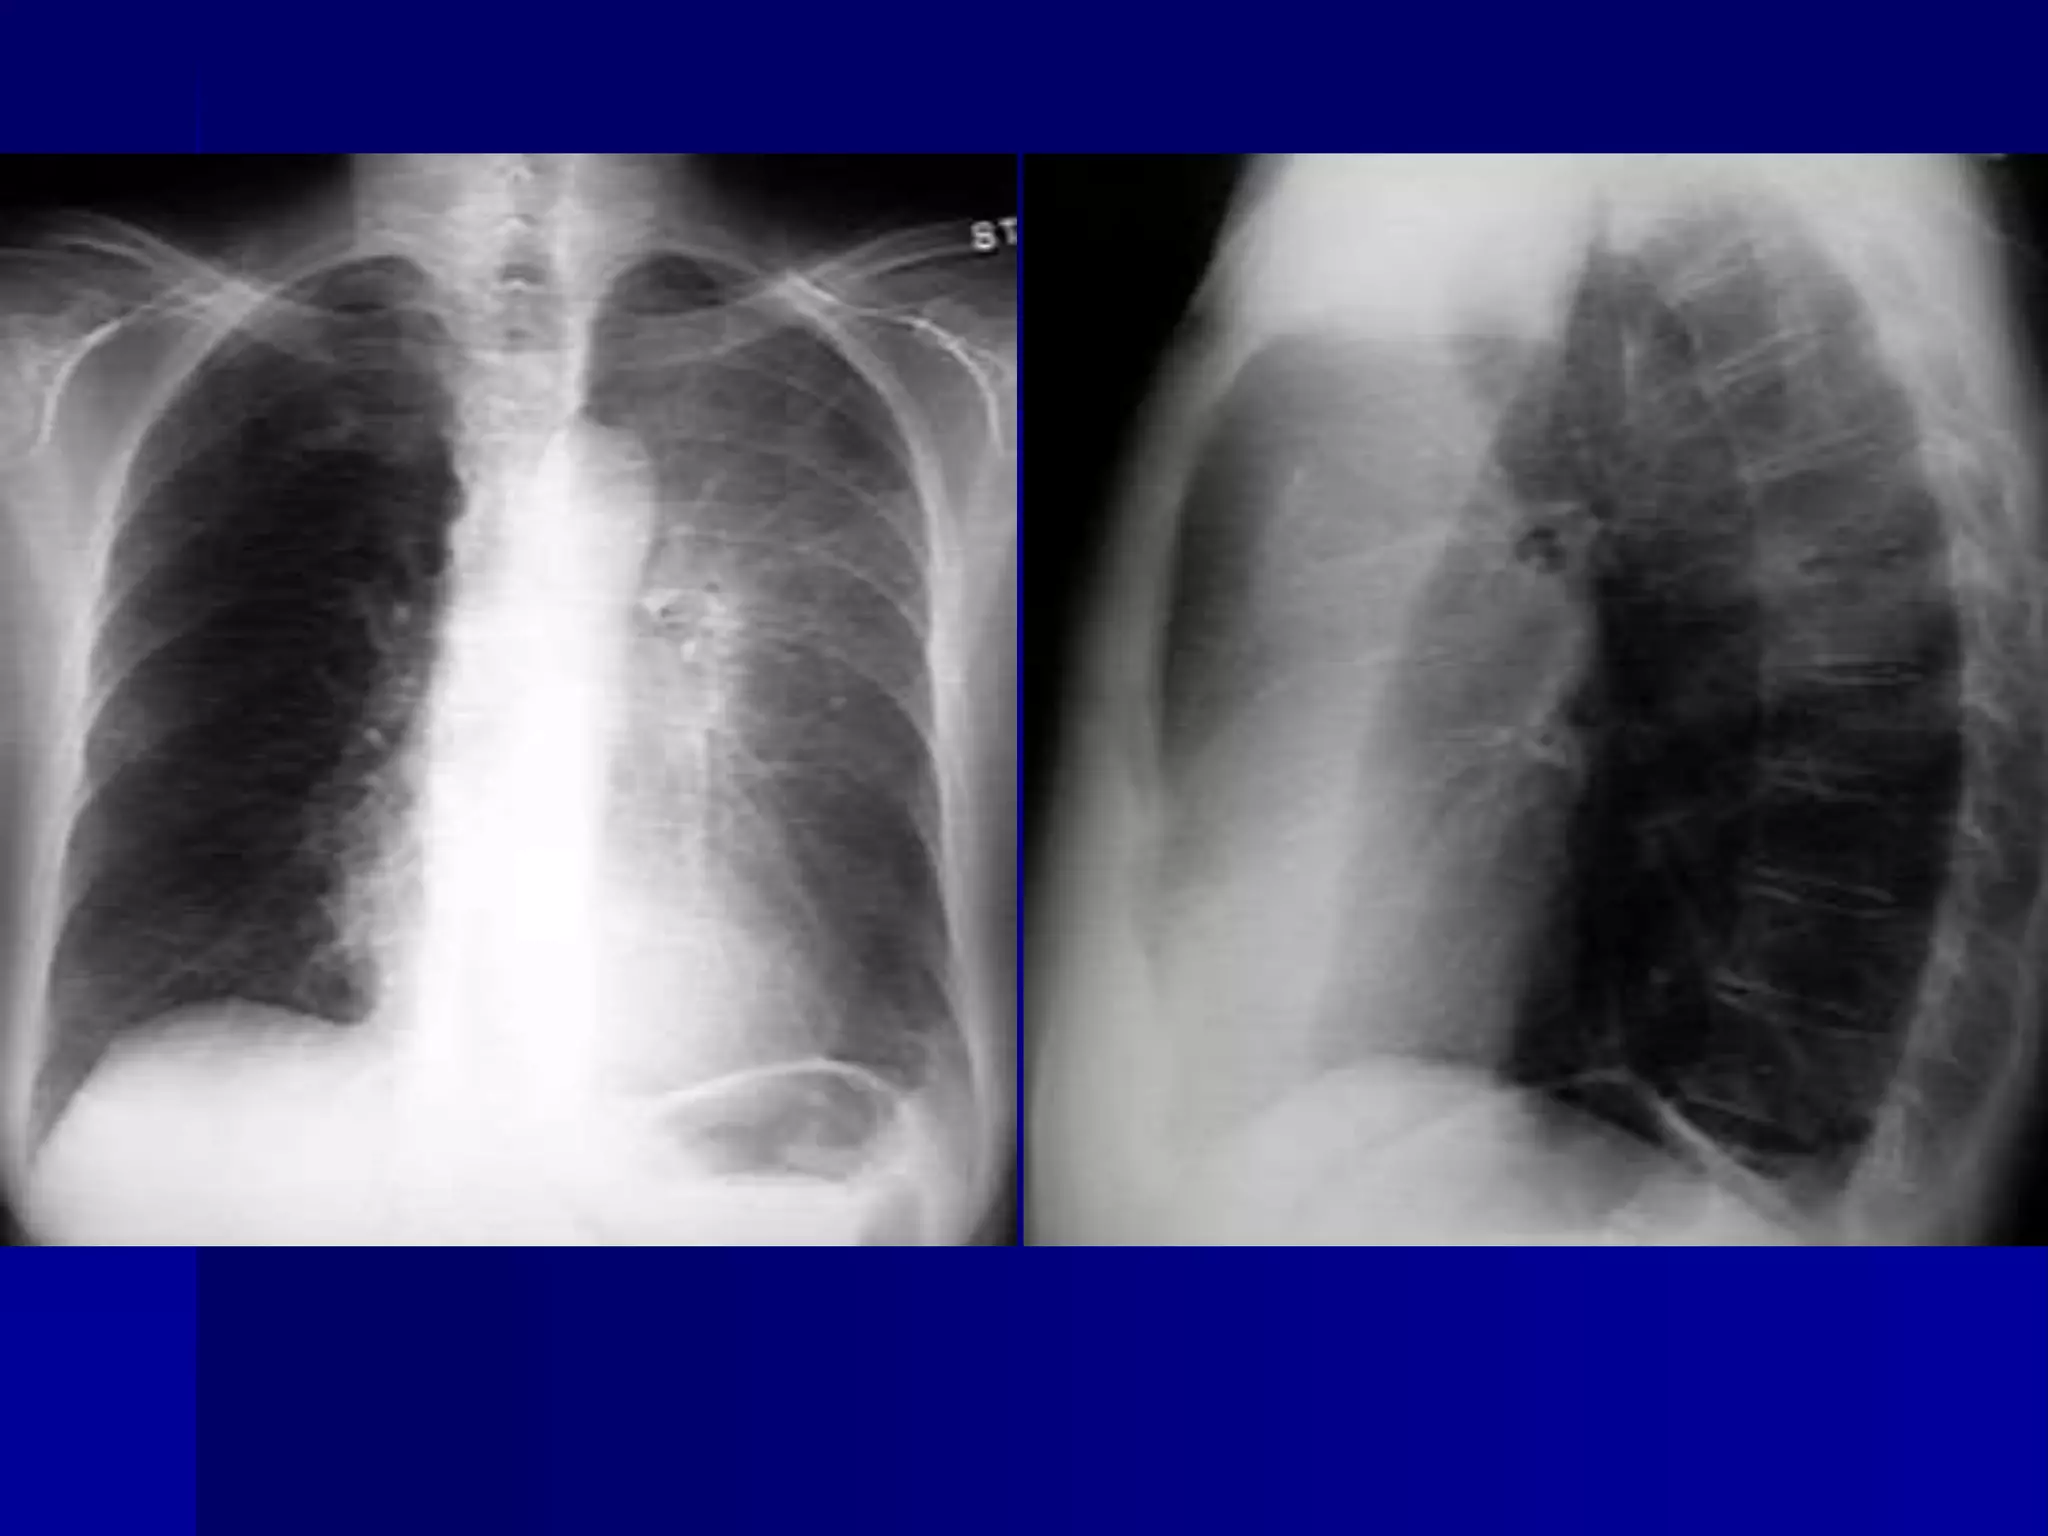

Atelectasis Right Lung

 Homogenous density right hemithorax

 Mediastinal shift to right

 Right heart and diaphragmatic

silhouette are not identifiable

 Atelectasis Right Lung

 Open Bronchus Sign

 Right heart and diaphragmatic silhouette

are not identifiable